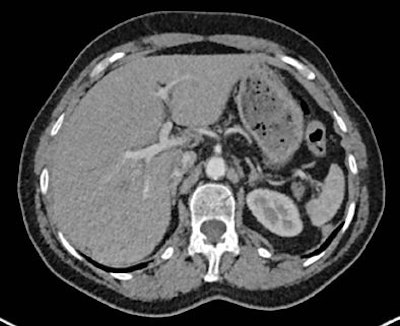

Images of the upper abdomen reconstructed using filtered backprojection (FBP) and the sinogram affirmed iterative reconstruction (SAFIRE) algorithm. Above, transverse image reconstruction with standard FBP at the level of the upper abdomen shows a high level of image noise. All images courtesy of Dr. Alkadhi Hatem.

Image reconstruction with raw data-based SAFIRE shows markedly reduced image noise and sharper depiction of vessel contours.Half the dose with far less noise